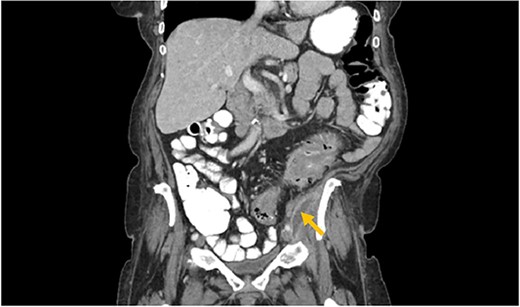

A 73-year-old female with past medical history of hypertension, diabetes mellitus, hyperlipidemia, recent history of complicated sigmoid diverticulitis with psoas abscess measuring 1.4 cm × 6.5 cm (Images 1 and 2). Patient underwent interventional radiology drain placement in the abscess cavity and antibiotic treatment with adequate response and was discharged home with oral antibiotics. Her last colonoscopy was 1 year prior, with no evidence of polyps. She followed up after 10 days with our colorectal surgeon. She denied any pain, her drain output was minimal. She was offered surgical intervention, however she refused. Drain was removed. She presented to the hospital again after 3 weeks with lower abdominal pain with radiation to left back and with anterior left upper thigh pain. She felt a sensation of fullness in that area. She was tolerating diet and having normal bowel movements. She denied any fevers, chills, urinary complaints. On the physical exam, her abdomen was soft, non-distended, there was tenderness to palpation in her left lower quadrant, no rebound, no rigidity. There was also severe tenderness to palpation in the left antero-lateral thigh. There were no skin changes, crepitus to palpation or drainage from this area.

Arrows shows extension of psoas abscess through abdominal wall in the surrounding tissues around the hip. There is not Hip bone involvement. Circle shows abscess next to the hip.